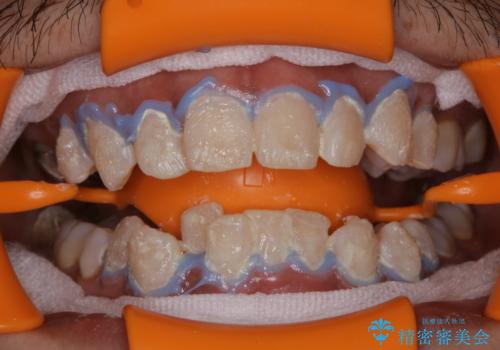

ホワイトニング

ホワイトニングは、歯を削ったり、傷つけたりすることなく歯の内部の象牙質まで浸透し、色素を分解して漂白することで、くすることができます。

ホワイトニングには歯科医院で行うオフィスホワイトニングと、ご自宅で行うホームホワイトニングがあります。

当法人ではプラン内容が細かく分かれていますので、ご自身に合わせたホワイトニングプランを立てることができます。